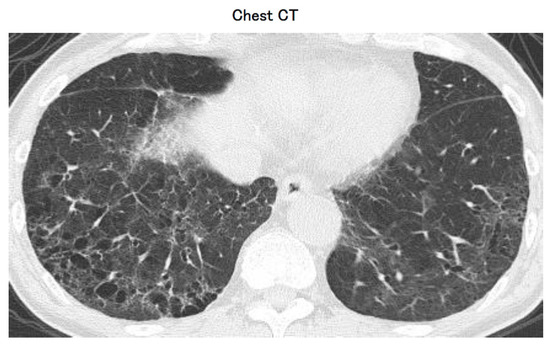

| Chest radiograph (A) and chest CT (B) are shown separately (Figure 1). |

The correct answers are a. Ventilatory management and d. Corticosteroids, which are the two options appropriate at this time. The patient was presenting with dyspnea, fever, and dry cough, which are symptoms that are commonly associated with COVID-19. The PCR test for SARS-CoV-2 using saliva was positive, confirming the diagnosis. The patient had a low oxygen saturation level (SpO2 93%) despite oxygen administration, indicating hypoxemia. Coarse crackles were heard in the lower thoracic region on the bilateral dorsal surfaces, and chest imaging revealed bilateral ground-glass opacities and consolidations, which are typical findings for COVID-19 pneumonia. The patient had an elevated PT-INR level of 2.4, which indicates a coagulopathy. This may be associated with the hyperinflammatory state induced by COVID-19, which can lead to a prothrombotic state. Given the severity of the patient’s symptoms and the hypoxemia, ventilatory management is appropriate, which may include non-invasive ventilation, high-flow nasal cannula, or mechanical ventilation.

Corticosteroids are recommended in the treatment of severe COVID-19 pneumonia, as they have been shown to reduce mortality and the need for mechanical ventilation in hospitalized patients. The patient’s CRP level of 10 mg/dL indicates a high level of inflammation, which further supports the use of corticosteroids. Antifibrotic drug administration, bronchoscopic lung biopsy, and oral cyclophosphamide are not appropriate at this time, as there is no evidence supporting their use in the management of COVID-19 pneumonia.